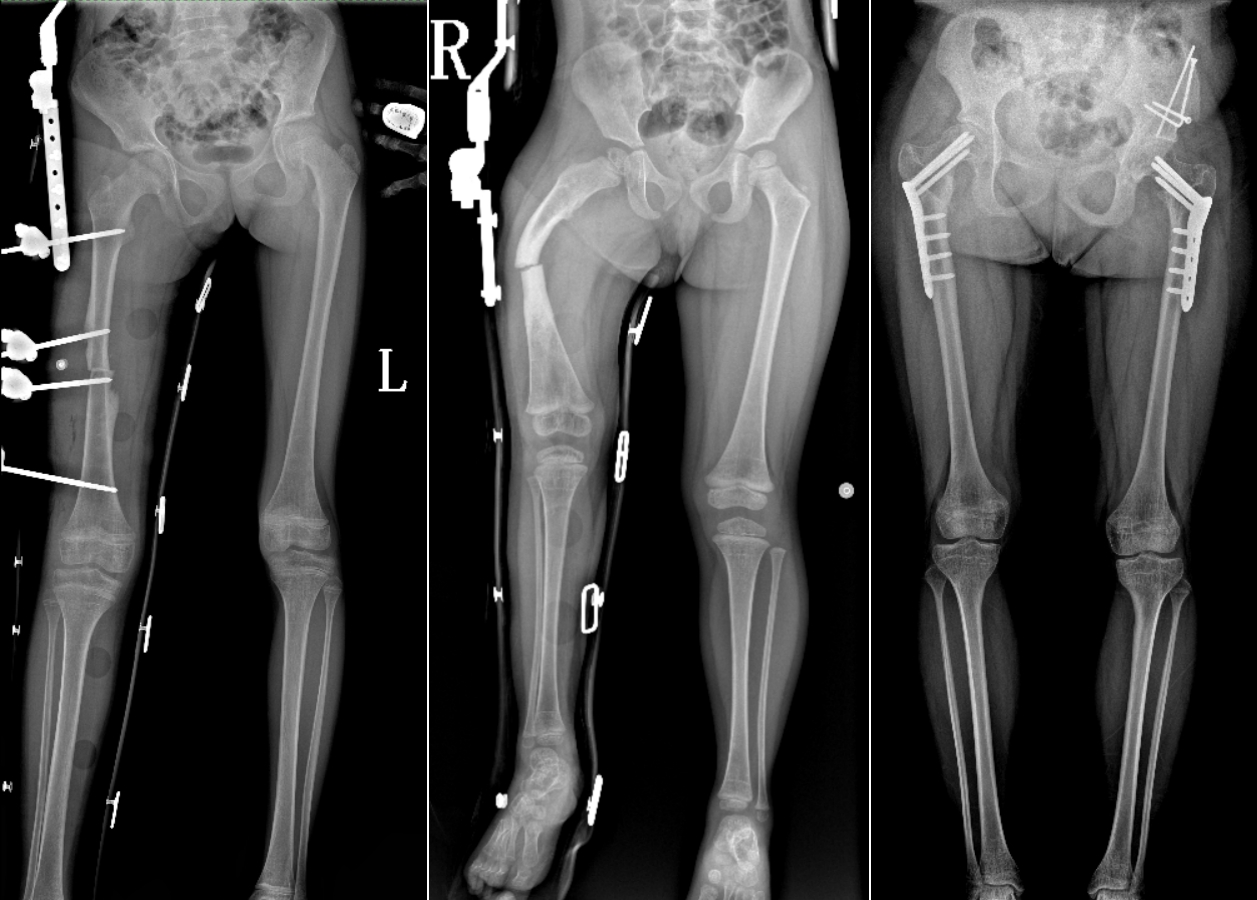

DR是臨床骨科的重要檢查手段之一。在骨科檢查中,脊柱矯形、長骨骨折、腰椎退行性病變等,需要采集脊柱、下肢全景圖像,輔助醫(yī)生臨床診斷,從而制定科學(xué)的治療方案,普愛醫(yī)療的大視野平板動態(tài)DR就像是一座橋梁,連接起現(xiàn)代醫(yī)療技術(shù)與當(dāng)?shù)厝嗣竦尼t(yī)療需求。

普愛醫(yī)療自主研發(fā)的大視野平板動態(tài),采用17"*34"的有效視野,一次曝光即可得到全脊柱或全下肢影像。相較于多張攝影再軟件拼接的DR設(shè)備,PLX8600解決了拼接圖像存在密度不均勻,拼接處圖像配準(zhǔn)和放大效應(yīng)等問題,給臨床帶來了真正的大視野影像解決方案。

除了常規(guī)靜態(tài)攝影外,PLX8600的大平板具備動態(tài)透視和點片功能,能夠很好地觀察復(fù)雜部位病灶,有效地抓取關(guān)鍵幀,降低患者多次攝片的概率。如:全脊柱狀態(tài)評估、長骨關(guān)節(jié)活動度、下肢靜脈造影瓣膜功能評估、消化道功能評估、脊髓造影等更多大視野臨床應(yīng)用,“多面手”都能輕松應(yīng)對。